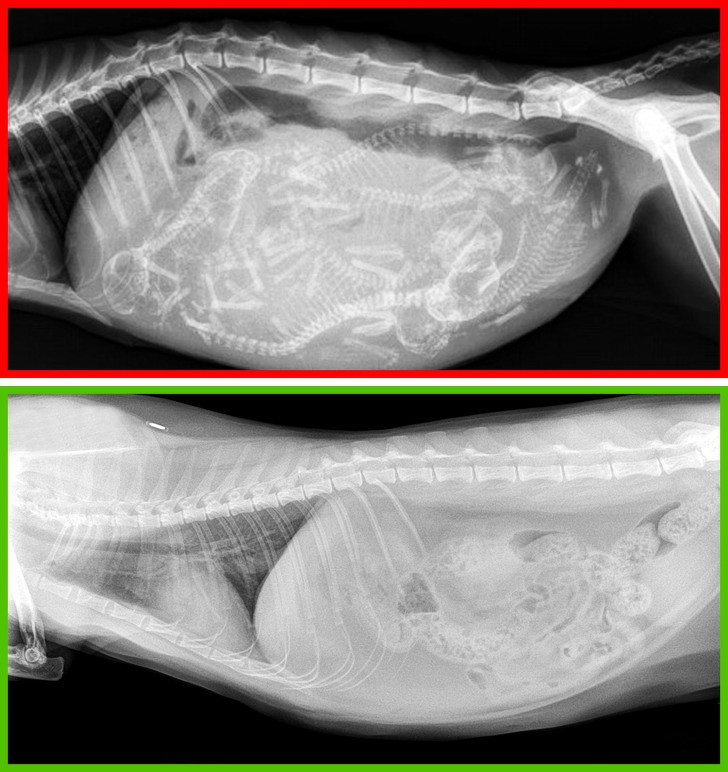

Trong hầu hết các trường hợp, triệt sản có tác động tích cực đến sức khỏe của mèo. Ngoài làm giảm nguy cơ gây ra các khối u ở hệ sinh sản, triệt sản khiến mèo thuần tính hơn và tránh trường hợp mèo trốn nhà đi chơi.